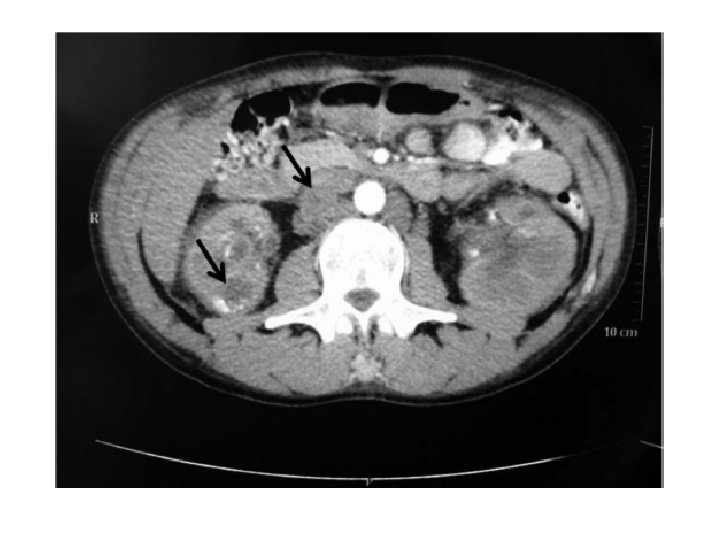

Imagem • RX de tórax: • Velamento de seio costofrênico esquerdo • Ultrassonografia renal: • Rim D pequeno com calcificações • Rim E aumentado, com hidronefrose e redução de parênquima • Solicitadas tomografias de abdome e tórax